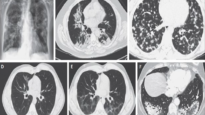

Lung Abscess Mediube Subscribe Subscribed 3 1173 videos 0% 34 Views 0 Likes 2025-01-22 PulmonologyImagingX-Ray By Mediube 0 Comments (بازدید 34 بار, بازدیدهای امروز 1 ) Show more PREV Lung Abscess Mediube 2025-01-22 NEXT Lung Infections Lung Abscess, Empyema, Fistula, Aspiration Syn Mediube 2025-01-22 You might be interested in 0 Home Sputum Collection Mediube 2024-05-21 0 Anatomy of the Endotracheal Tube ET Tube Airway Management Mediube 2025-02-24 0 Lungs_ Definition, Location Structure Mediube 2024-09-28 0 Teaching lung sound auscultation and diagnosing lung problems based on its sound – part 1 Mediube 2024-01-31 0 Pneumonia Mediube 2024-07-24 0 understanding tuberculosis Mediube 2025-10-05 0 Thoracentesis Mediube 2024-04-27 0 Unraveling BOOP- A Deep Dive into BRONCHIOLITIS OBLITERANS Organ Mediube 2025-04-22 0 Ace Your Respiratory Examination OSCE With This Clinical Skills Mediube 2024-12-23 0 Pneumonia (Right Middle Lobe): Explanation of Chest X-ray Findings Mediube 2024-04-15 0 Top 10 WARNING signs of Lung Cancer Mediube 2024-09-30 0 How to Interpret a Chest X-Ray (Lesson 8 – Focal Lung Processes) Mediube 2024-04-14 LEAVE YOUR COMMENT Cancel replyYour email address will not be published. Required fields are marked * Save my name, email, and website in this browser for the next time I comment. Δ